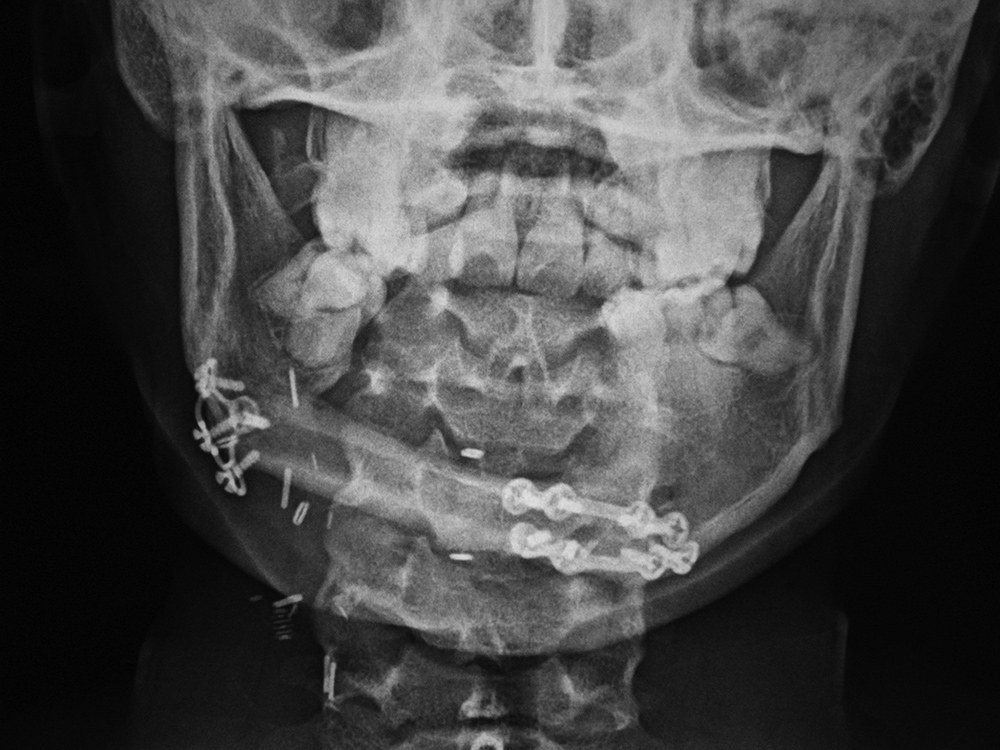

Mandibular reconstruction

25 year-old woman with mandibular osteosarcoma. The mandible was restored with autologous fibula free-flap reconstruction.